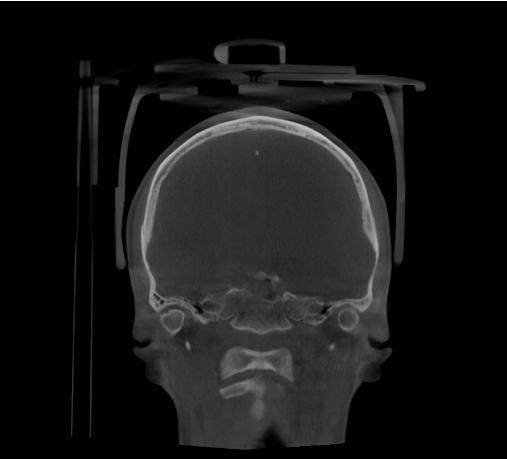

Imagen 1: Vista coronal de CBCT de cráneo completo para cirugía ortognática (FOV 23×26). Imagen aportada por RD3D.

El CBCT 3D permite obtener una imagen tridimensional completa del esqueleto facial, ofreciendo información milimétrica sobre la posición de huesos, dientes y articulaciones.

- Reconstrucciones 3D realistas del cráneo y la mandíbula.

- Evaluación de asimetrías faciales y relación entre maxilares.